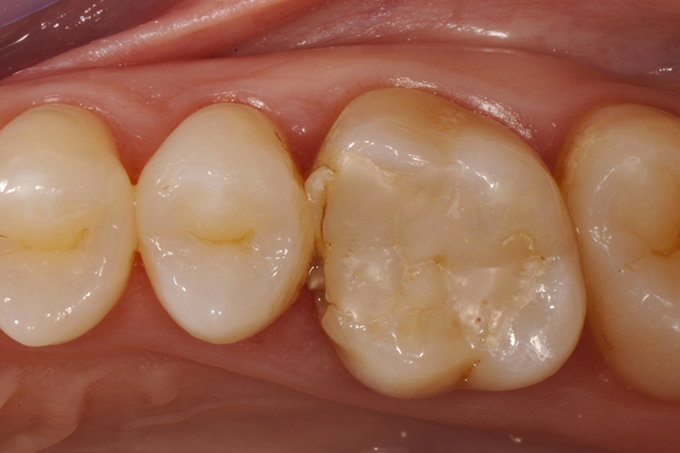

Build-up with remodeled margin (according to Dietschi, D., Spreafico, R., 1997) and final preparation of the tooth.